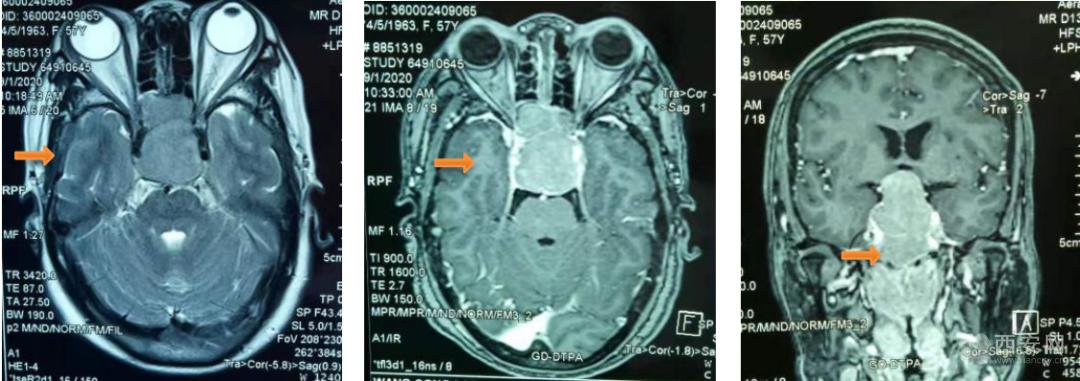

(手术前MR显示鞍区巨大肿瘤侵犯双侧颈内动脉 向上挤压第三脑室,下突入鼻腔)

检查结果显示为巨大侵性垂体腺瘤,肿瘤生长向上突入鞍上池,向下突破鞍底蝶窦进入鼻腔破坏颅底斜坡骨质,大小约31×38×32mm,属于罕见的巨大型侵袭性垂体腺瘤。